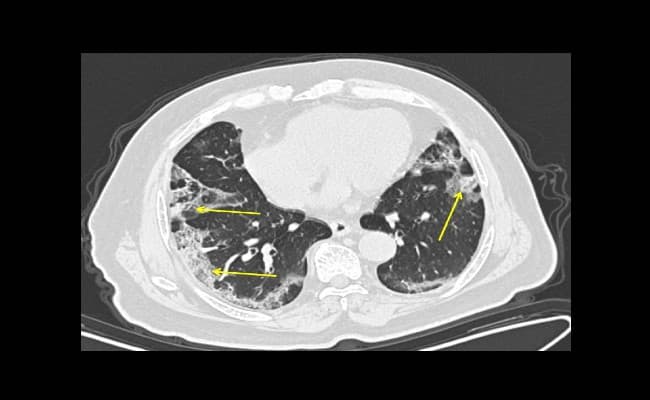

रेडियोलॉजिकल सोसाइटी ऑफ नार्थ अमेरिका (RSNA) ने एक तस्वीर जारी की है.जिसमें फेफड़ों के सीटी स्कैन और एक्स-रे से यह सामने आया है कि संक्रमित मरीजों के फेफड़े चिकने और गाढ़ी बलगम से भर जाता है. इस कारण संक्रमित व्यक्ति की सांस घुटने लगती है क्योकि फेफड़ों में हवा के जाने के लिए कोई जगह नहीं बचती.

कोरोनावायरस से संक्रमित मरीजों के सीटी स्कैन से उनके फेफड़ों में सफेद धब्बों का पता चला है. जिसे रेडियोलॉजिस्टों ने अपनी भाषा में ग्राउड-ग्लास ओपेसिटी कहा है. क्योंकि वे स्कैन की गयी 3D तस्वीरों में खिड़कियों में लगे धब्बों जैसे दिखायी देते है. संक्रमित मरीजों के फेफड़ो के सीटी स्कैन से ऐसे लक्षण नजर आए है जो निमोनिया के होते है. लेकिन कोरोना के केस में ये कुछ ज्यादा ही गाढ़े है और फेफड़ो में हवा की जगह कुछ ओर ही भरा हुआ नजर आया

इस 3D इमेज से दुनियाभर के डाक्टर एक्स-रे और सीटी स्कैन से कोरोना से संक्रमित मरीजों की जल्दी पहचान कर पाएंगे जो गंभीर रूप से संक्रमित है और उन्हें तुरंत आइसोलेट करने में आसानी होगी . चीन के वुहान शहर से फैला कोरोना वायरस अब तक 125 से ज्यादा देशों को अपनी चपेट में ले चुका है. वहीं दुनियाभर में 4660 से ज्यादा लोग मारे गए है और 1 लाख 26 हजार से ज्यादा लोग संक्रमित है.